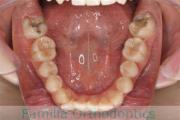

No.22V-029

- 叢生

- 上顎前突

- 19歳

- 男性

- 抜歯部位

- 上:

- 8448

- 下:

- 主な使用装置:

- FEA 022

- 治療にかかった費用:

- 92万円

でこぼこを治したいということで来院されました。上下左右から親知らずも第一小臼歯も抜歯が必要で、歯科矯正アンカースクリューを併用して大臼歯を後ろに引っ張りながらの治療でした。3年弱、35回程度の通院が必要でした。

叢生が著しく、後戻りのリスクがあります。またアンカースクリューが必須のため、もしもスクリューが安定しないと、治療が難しく長くなってしまう恐れがありましたが、幸い脱落は見られませんでした。

- ≫治療後

-

上顎

下顎